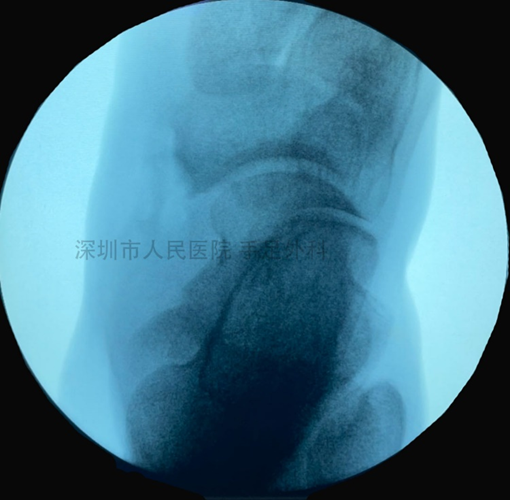

图8:舟骨置入锚钉,重新固定胫后肌腱止点。